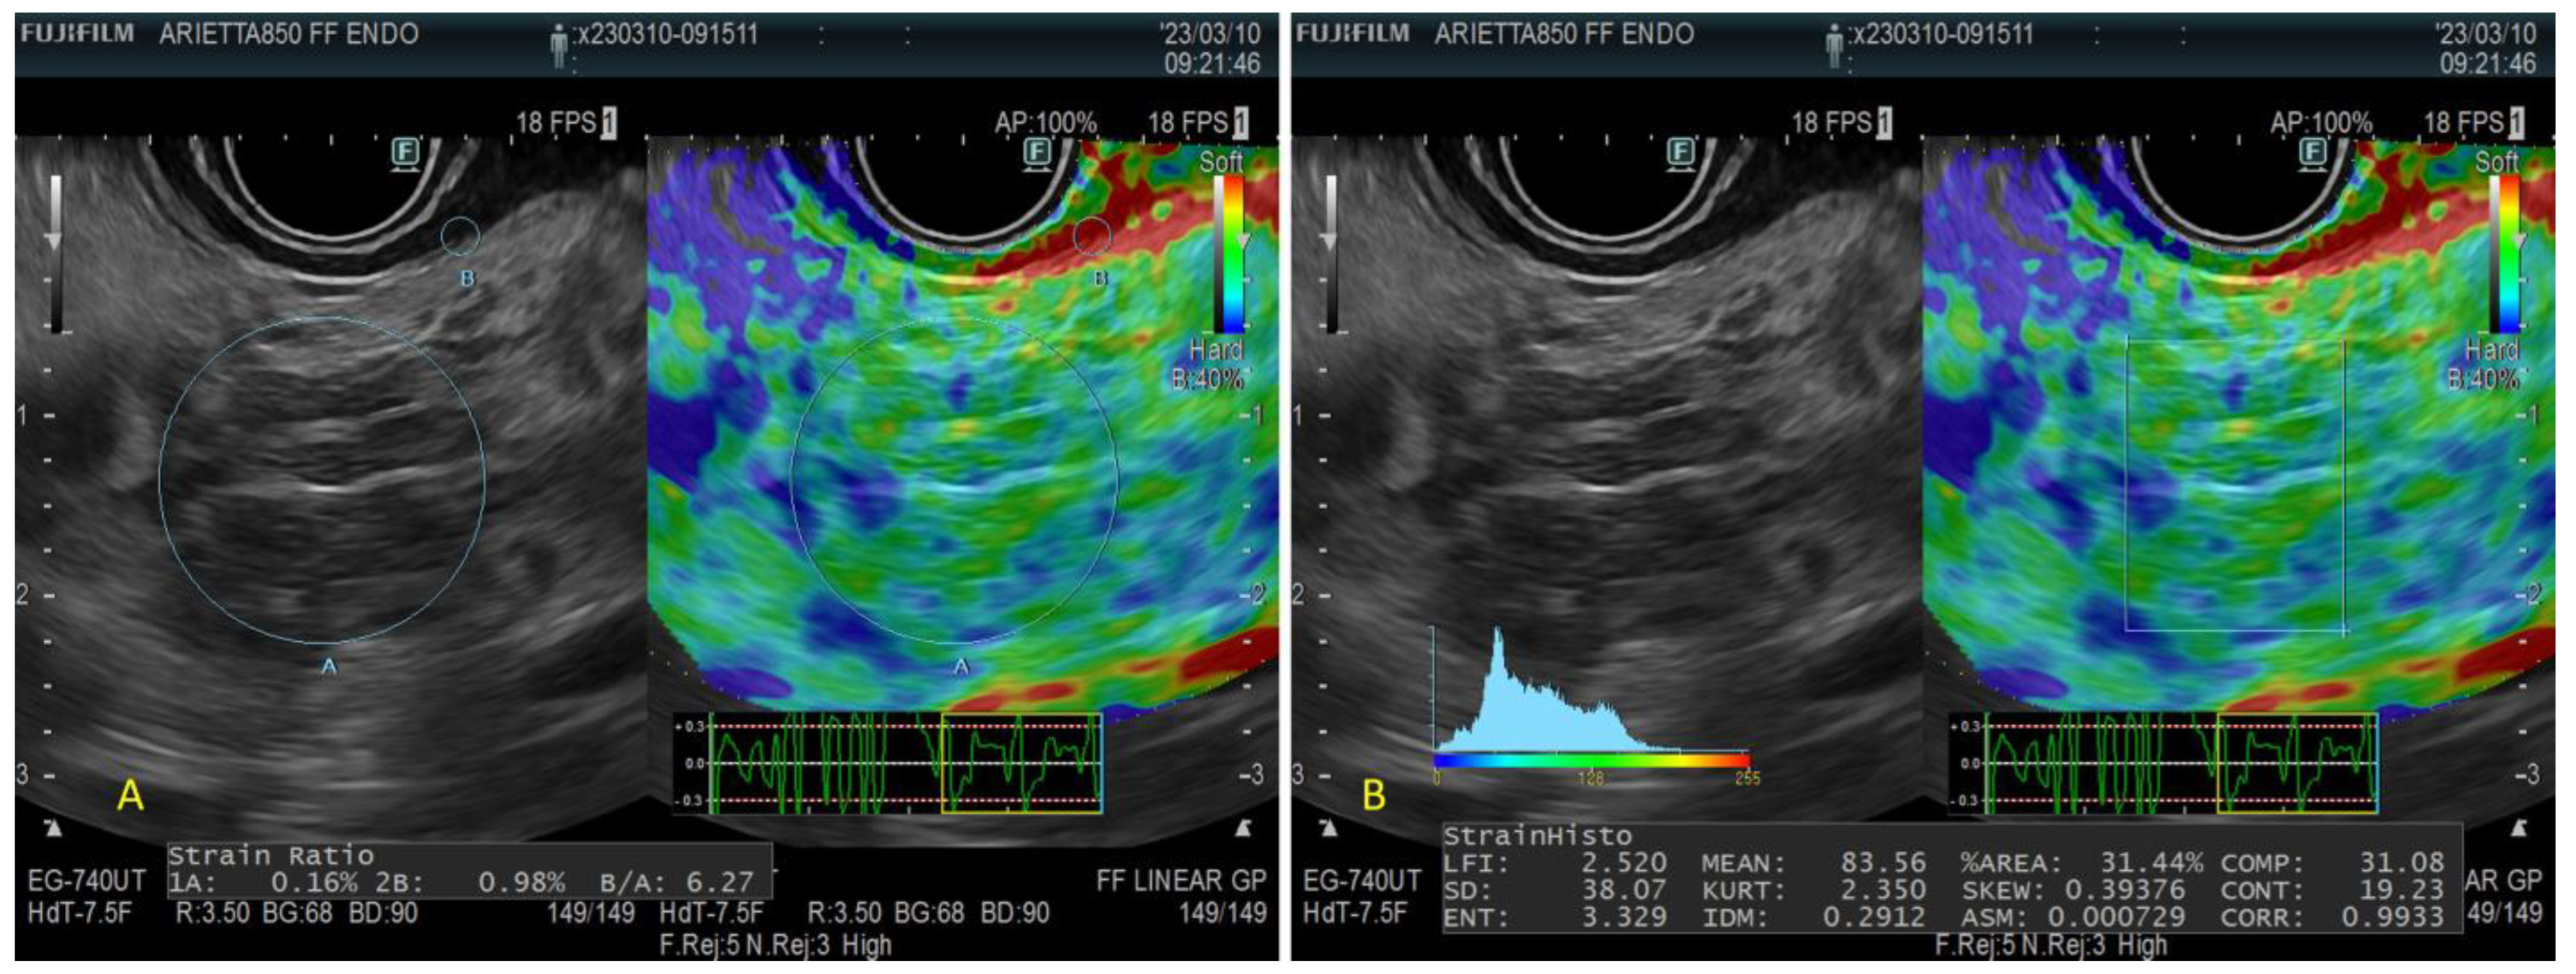

- Quantitative Strain Elastography

- Strain Histogram

- Strain ratio